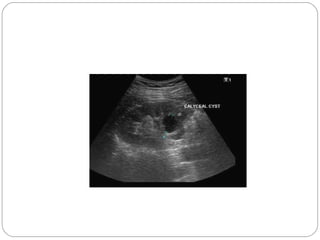

CALYCEAL CYST (DIVERTICULUM)

An intraparenchymal cavity lined by transitional

epithelium which communicates with a minor

calyx, either centrally or at fornix

Do not receive any drainage from nephrons

IVU – well defined opaque rounded area adjacent

but peripheral to a minor calyx

D/D – small cyst & hydrocalyx

RISK – calculus, infection & hematuria